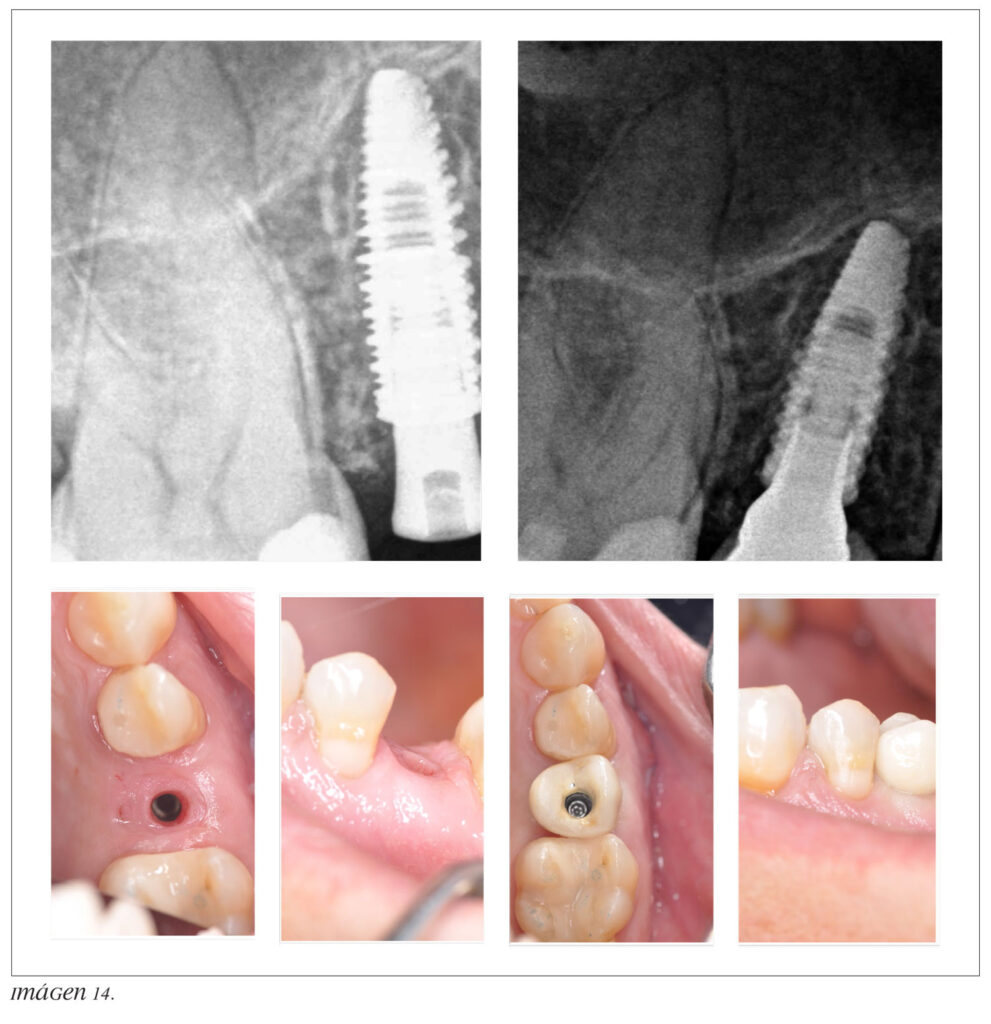

La muela está dividida verticalmente en dos mitades iguales.